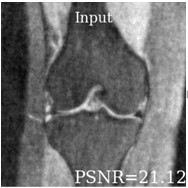

Deep learning based techniques achieve state-of-the-art results in a wide range of image reconstruction tasks like compressed sensing. These methods almost always have hyperparameters, such as the weight coefficients that balance the different terms in the optimized loss function. The typical approach is to train the model for a hyperparameter setting determined with some empirical or theoretical justification. Thus, at inference time, the model can only compute reconstructions corresponding to the pre-determined hyperparameter values. In this work, we present a hypernetwork based approach, called HyperRecon, to train reconstruction models that are agnostic to hyperparameter settings. At inference time, HyperRecon can efficiently produce diverse reconstructions, which would each correspond to different hyperparameter values. In this framework, the user is empowered to select the most useful output(s) based on their own judgement. We demonstrate our method in compressed sensing, super-resolution and denoising tasks, using two large-scale and publicly-available MRI datasets. Our code is available at https://github.com/alanqrwang/hyperrecon.